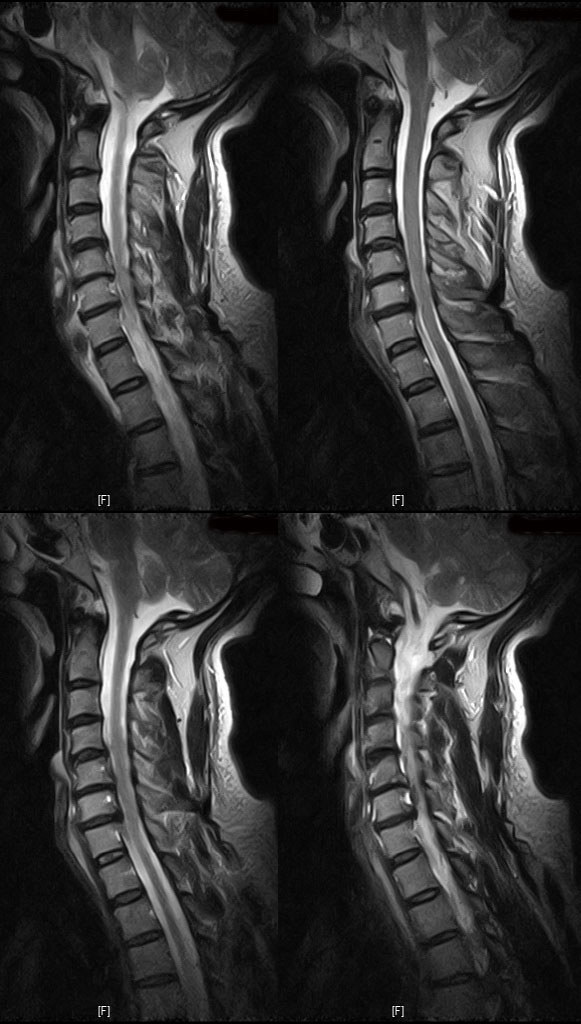

--Դ 㳻-- ** ڰ , *** ġغ ϰ ֻ̿ °Դٰ , ȸԲ MRI ǵ Ŀ μ ̳ ġ ɼ ſ ٰ Ͻð 迵ռ̳ ƹ ġ Ͻð ϶ ϼ̽ϴ. 迵 Բ ϼ̽ϴ. -----------5 ı ȿ ----------- ũ ǥغ no 3823 date 2009-06-08 name *ȣ (*****58110@hanmail.net) IP: 122.34.108.171 523 溴 MRIԿ Ͽµ ũ(5-6 ߰Ż, 6-7 ߰)̶ Ҿ ٷ ؾѴٴ ǻ Ը ũ O 츮麴 Ͽ Ͽ Ȱҽϴ, ٸ 츮麴 ġḦ ް Ȳ Ѻ θڴ ǻ缱 ֻ ุ óް MRI Ұ ϴٴ° ˰ ֱ Ǿ ͳ ˻ϴٰ 쿬 ǥغ˰ԵǾ 62ϳ (160ȣ)ϰ (迵ռ) ģ 뼳 ħ ݱ ϰִϴ. . .չٴ.հ Ҷ Ⱘ ѰͰ ̿ . ̺ ̿ϴ. ǥغ 2Ϻ ݱ(7ϰ) .. Ⱥ ձ ϸ ϵǾ ȿ ̾ ͵ Դϴ. ȿ հ ̾ ӵǾ 8ϳ Ʈ Ͽϴ. µ ϱ ٴڿ ִ ̺ڸ ̰ ʾ Ʈ Ͽ ڽ ũ ʰ غڴٴ ҸغŴϴ. MRI ÷ ũ ȯں غ. 61 5 Ҿ 1ð Ӻ ȱ⸦ ϸ ǽ ٸڼ ϸ ƴƴ ƮĪ ǰ ð ִϴ. ó ũ ȯں Ŵٸ ǥغ غð ϴ ٷԴϴ. Ʈ Բ غ ٽñ ۿø ϰڽϴ. ݵ ǰ Ѱô. ȭ!!! ---------------------- Ű Ű169 ü65 52 ˰Ե ͳ ˻ڷ õ --------------ǥغ ---------------- ش 1C., 1C.ڵӸ 1C.ٸǷ 2C.ڽ÷ 3C. 4C.5C.ھ, հ 5C.6C.ڰ հ ̳ 6C.ھ Ḳ 6C.ڻ 6C.7C.ھ հ ̳ 1T.ڼո 1T.ڼհ ü ̳ 1T.꿪 ĵ 5T.氣 5T.ھ ȯ 6T., 6T.ټ 6T.ٽƮ 6T.꿪 ĵ 7T.˾ 10T.ٸǷ 3L.̻ 3L. 3L.ڹ 3L. 4L Һ Һ 4L. ̻ 4L.° ()ũ( ߰Ż) ߺ ༺ ũ ũ(߰) Ը ũ(߰Ż)ġ, հ , ġ, , Ḳ ġ Ǵ ġ ô , 㸮 ̳ ġ ħ , dz, , Ǵ ġ Ƿ ġ γ Ȱ ϰ Ѱ . ..( ⰨȰó Ҷ ִ) 1)()ũ( ߰Ż) 2)()ũ( ߰) --Դ 㳻-- ** ڰ , *** ġغ ϰ ֻ̿ °Դٰ , ȸԲ MRI ǵ Ŀ μ ̳ ġ ɼ ſ ٰ Ͻð 迵ռ̳ ƹ ġ Ͻð ϶ ϼ̽ϴ. |